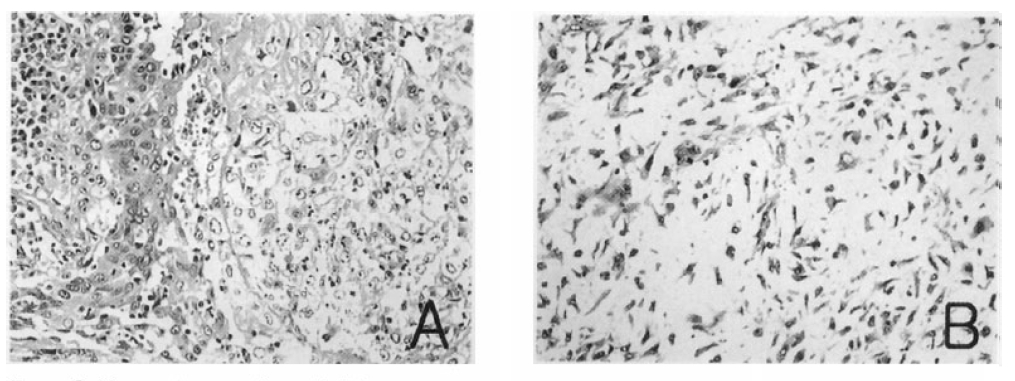

To define the exact etiology of the radiologic findings, thoracoscopic wedge biopsy of the left lower lobe demonstrated the mass to be contained within the lateral basal segment and the medial basal segment of the left lower lobe. On gross section, the mass was 10×9×7 cm in size, sharply circumscribed and smoothly contoured. It had no involvement to the chest wall and no endobronchial component, but extended centrally to hilar areas. Light microscopic examination demonstrated a tumor composed of malignant epithelial components and mesenchymal components. The carcinomatous components consisted of poorly differentiated squamous cell carcinoma and the sarcomatous components were considered chondroid sarcoma in the light of microscopic findings (Figure 3). Light microscopic immunohistochemical analysis showed that the tumor cells in the carcinomatous component reacted with anti-epithelial membrane antigen (EMA) antibody and the tumor cells in the sarcomatous component reacted with anti-vimentin antibody (Figure 4). He underwent workup for distant metastasis, the findings of which were unremarkable. Therefore, left lower lobectomy was performed with lymph node dissection. There was no microscopic evidence of lymph node metastases making this the international TNM stage lb (T2N0M0) lesion.

Figure 4.

Immunohistochemical stainings. The poorly differentiated squamous cell carcinoma shows focal positive for epithelial membrane antigen (A). The chondrosarcoma shows positive for vimentin (B). (× 400)